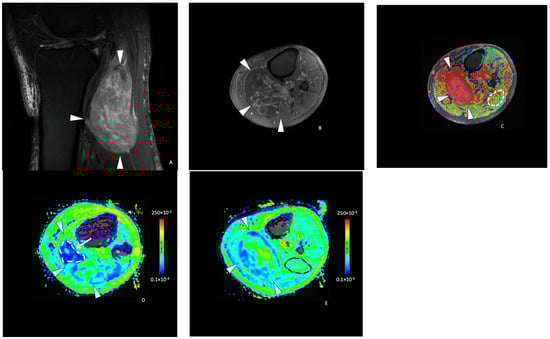

The median ADC value in the STS studied was 134.3 (101.7–167.9) × 10−3 mm2/s. The median tumor-to-muscle ADC ratio was 1.00 (0.77–1.55). There was a significant correlation between the ADC value and the post-treatment tumor necrosis percentage (p = 0.013) with a fair Spearman correlation coefficient (0.47). There was also a statistically significant correlation between the tumor-to-muscle ratio ADC and the post-treatment necrosis percent (p = 0.011) with a 0.48 Spearman correlation coefficient. Among the 20 tumors with less than 50% necrosis after RT, the median ADC value was 120.3 (97.7–161.6) × 10−3 mm2/s (Figure 3), while in tumors with more than 50% necrosis, the mean ADC value was significantly higher: 202.0 (160.9–243.6) × 10−3 mm2/s (p = 0.020) (Figure 4). For tumor-to-muscle ratio ADC, the difference was also significant with median ratios of 0.93 (0.72–1.25) and 1.55 (1.18 to 1.81) for tumors with under and over 50% of histologic necrosis (p = 0.045).

Figure 4.

A 63-year-old female with a liposarcoma issue of the left thigh. Axial T1-weighted (A), T2-weighted fat-saturated (B), and T1-weighted contrast-enhanced (C) MR images showing a large heterogeneous tumor (arrowheads) of the posterior compartment of the thigh, arising from the semitendinosus and semimembranosus muscles containing hemorrhagic components (hyperintense signal T1, arrow in (A), a fat portion on its medial side (star in (A,B)) and small areas of intratumoral necrosis (arrow in (C)). (D) Axial ADC functional map showing a tumor with high ADC value measured at 288 × 10−3 mm2/s in the white dashed lined ROI (>161 × 10−3 mm2/s). The tumor necrosis percentage after neoadjuvant therapy was 60%.